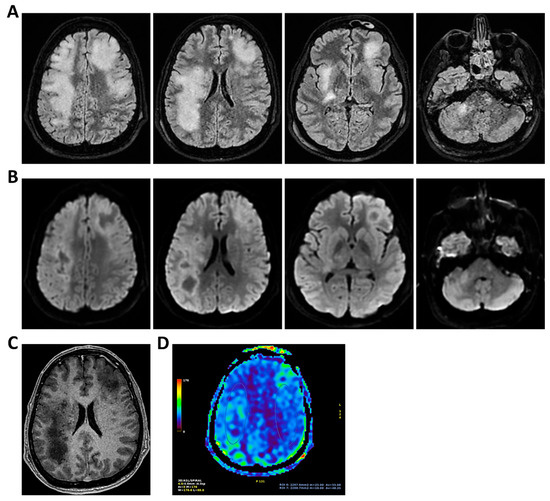

Figure 4.

MRI of patient 4 group 1. A 46-year-old HIV-positive woman with a history of substance abuse, alcohol use, heavy smoking, and on methadone therapy was admitted to the ER after a fall with head trauma. Cranial CT revealed a hypodense, heterogeneous lesion in the right nucleus-capsular region. Chest CT showed pseudonodular lesions, parenchymal consolidations (lingular and posterior-basal left lung), bilateral fibrous-scar tissue thickening, and polylobulated thickening in the right upper lobe. Due to respiratory deterioration, she was intubated and admitted to the ICU. Infectious disease consultation revealed severe immunosuppression (CD4 count 37/mm3), high HIV and HCV viral loads, and positive toxoplasmosis serology. She was not on antiretroviral therapy. Transferred to a specialized ICU, she was diagnosed with neurotoxoplasmosis. On day 2, TCCD showed altered CBF with PI of 1.96 on the right and 1.25 on the left, indicating possible intracranial hypertension. (A) 3D axial FLAIR sequence shows multiple bilateral supratentorial and infratentorial hyperintense areas. (B) Some of these areas present diffusion restriction in axial DWI sequence with the largest located in the right basal ganglia with moderate compression on the third ventricle. (C) One of these areas in the right middle frontal gyrus shows “ring enhancement” in the 3D axial T1 FSPGR after administration of contrast medium.